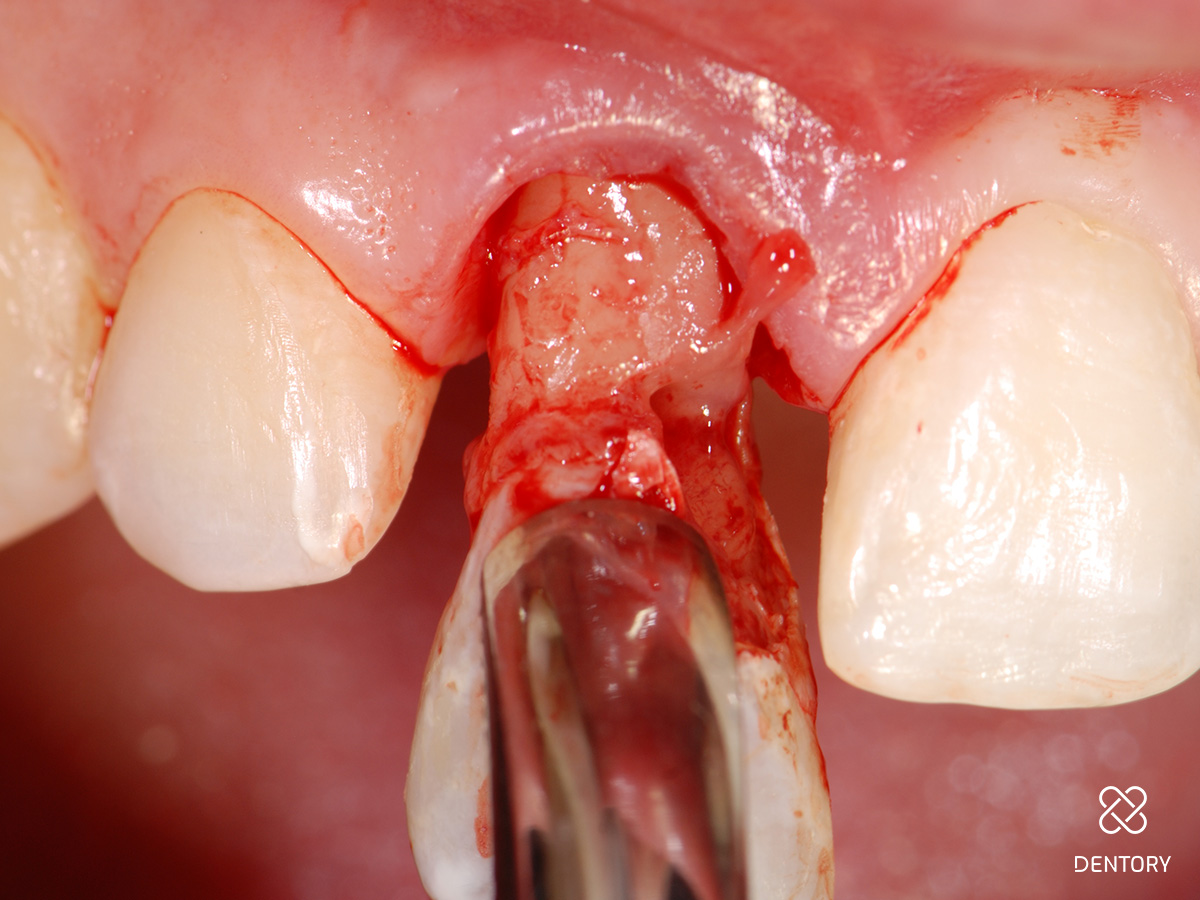

Abbildung 2

Schonende Zahnentfernung: Behutsames Durchtrennen der paradontalen Fasern mittels Mikroskalpell...

Abbildung 3

...und Entfernung des Zahns durch minimale rotierende Bewegungen mit der Zange.